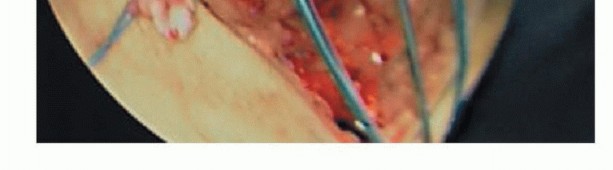

A medial parapatellar skin incision is made and the skin and sartorius fascia are kept as one layer (TECH FIG 6A,B).

Working between the window of the upper and lower border of the hamstrings the tibial insertion of the superficial MCL and the POL central arm sites are marked. The femoral insertions of the superficial MCL and the POL central arm sites are also marked (TECH FIG 6C-F).

The tibial insertion of the superficial MCL is located 61 mm distal to the tibial plateau (TECH FIG 6C). The tibial tunnels should be tapped (TECH FIG 6D).

Two semitendinosus or tibialis tendon allografts are cut to 16 cm for the MCL, 12 cm for the POL (TECH FIG 6G).

The MCL and POL grafts fixed first on the tibial side with 7- × 25-mm bioabsorbable screws (TECH FIG 6H)

The MCL and POL grafts passed into their respective femoral tunnels and the medial reconstruction tensioned prior to ACL reconstruction.

TECH FIG 6 • A. Medial parapatellar incision is shown. B. Sartorial fascia shown elevated as one flap with the skin. Black arrow depicting sartorial fascia below skin. C. Tibial insertion of the MCL ˜61 mm distal to the joint line (red arrow). Semimembranosus tendon (green star). Tibial insertion of the central arm of the POL (blue arrow). D. Tibial tunnel tapped. E. Tibial insertion of MCL (black arrow), tibial insertion of the central arm of the POL (blue arrow), femoral insertion of MCL (green arrow), femoral

insertion of the central arm of the POL (yellow arrow), and superficial MCL (red star). F. Tibial insertion

of MCL (black arrow), tibial insertion of the central arm of the POL (blue arrow), femoral insertion of MCL (green arrow), femoral insertion of the central arm of the POL (yellow arrow), and superficial MCL (red star). Semimembranosus being retracted inferiorly to reveal tibial insertion of POL. G. Two semitendinosus or tibialis tendon allografts are cut to 16 cm for the MCL, 12 cm for the POL. H. MCL and POL grafts fixed first on the tibial side with 7- × 25-mm bioabsorbable screws. I-K. Grafts fixed with 7- × 25-mm bioabsorbable screws on the femoral side, with completed reconstruction. (B,F-K: Courtesy of Charles H. Brown, Jr., MD.)

MCL tensioned at 30 degrees, neutral tibial rotation, POL tensioned at full extension Grafts fixed with 7- × 25-mm bioabsorbable screws on the femoral side (TECH FIG 6I-K)